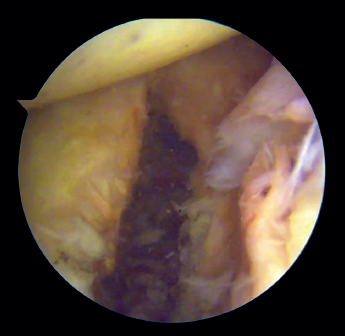

Introduction of the glenoid guide and positioning of the sheaths

(Figures 2 and 3)

Figure 2. View from the anterosuperior portal (left shoulder). Note the glenoid guide positioned at the centre of the defect and drilling at its upper and lower portion, spaced 10 mm apart.

Arthroscope is introduced through the anterosuperior portal, and the glenoid guide is introduced through the posterior portal, and passed paralel to the glenoid surface until the hook is located at the centre of the bone defect. The guide is secured with two cannulas inserted through two small accessory incisions, until connecting with the posterior cortical layer. Both cortical layers are drilled through them using a 2.8 mm drill fitted with a sheath so that on withdrawing the drill the sheath is positioned at drilling level. This step is made twice to introduce two sheaths: one above and the other below the glenoid guide hook and spaced 10 mm apart. Through these sheaths we advance two monofilament loops that are retrieved sequentially through the anterior portal for subsequent passing of the graft. At this point we can remove both sheaths and the glenoid guide, taking care to prevent the guide hook from coming into contact with the glenoid surface in order to avoid damaging to the cartilage.

Figure 3. View from the anterosuperior portal (left shoulder). Monofilaments inserted through the sheaths from posterior to anterior for subsequent passing of the threads that will introduce the graft.